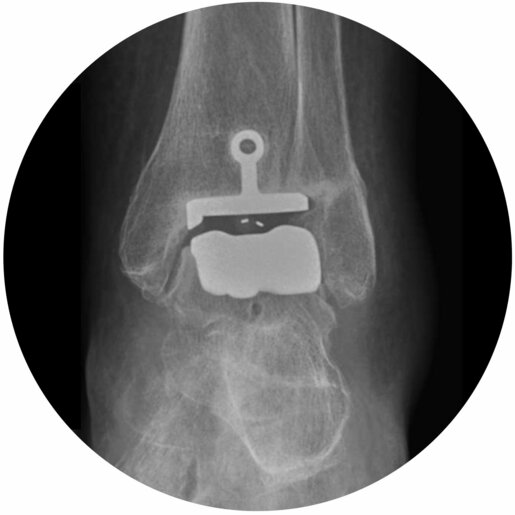

Oberes Sprunggelenk

Das obere Sprunggelenk ist für die Beweglichkeit des Beins und beim Laufen zur Durchführung der Abrollbewegung essentiell. Dabei überträgt sich das gesamte Körpergewicht auf eine circa 5x5cm große Gelenkfläche.

Eine primäre Arthrose, d.h. ein altersbedingter Gelenkverschleiß, im oberen Sprunggelenk ist im Vergleich zu anderen Gelenken (z.B. Hüftgelenk) eher selten, so dass meist sekundäre Arthrosen auftreten. Beispielsweise kann nach einem Bruch des Unterschenkels oder des Sprungbeines der Gelenkknorpel Schaden nehmen und das Gelenk dadurch dauerhaft verschleißen

In Abhängigkeit vom Ausmaß der Arthrose, d.h. ob möglicherweise noch angrenzende Gelenke betroffen sind, sowie vom körperlichen Anspruch des Patienten kommt der endoprthtetische Ersatz des oberens Sprunggelenkes oder die endgüktige Versteifung in Frage.

Abbildung links: Die Skizze zeigt die Konstellation der Knochen am Rückfuß. Hellblau = Schienbein, dunkelblau = Wadenbein, gelb = Sprungbein, grün = Fersenbein.

Abbildung mitte: Im CT stellt sich eine fortgeschrittene Arthrose im oberen Sprunggelenk (zwischen Schienbein und Sprungbein) sowie zwischen Sprung- und Fersenbein (Teil des unteren Sprunggelenkes) dar. Eindrücklich ist der aufgebrauchte Gelenkspalt sowie die knochenfreien Löcher an den Gelenklinien (sog. Geröllzysten).

Abbildung rechts: Seitliches Röntgenbild. Die Arthrose verursachte starke Schmerzen, weshalb die Versteifung der verschlissenen Gelenke mittels eines Titannagels durchgeführt wurde. Damit sind das obere und ein Teil des unteren Sprunggelenkes zwar fest miteinander verbunden, die Belastung ist jedoch wieder schmerzfrei möglich.